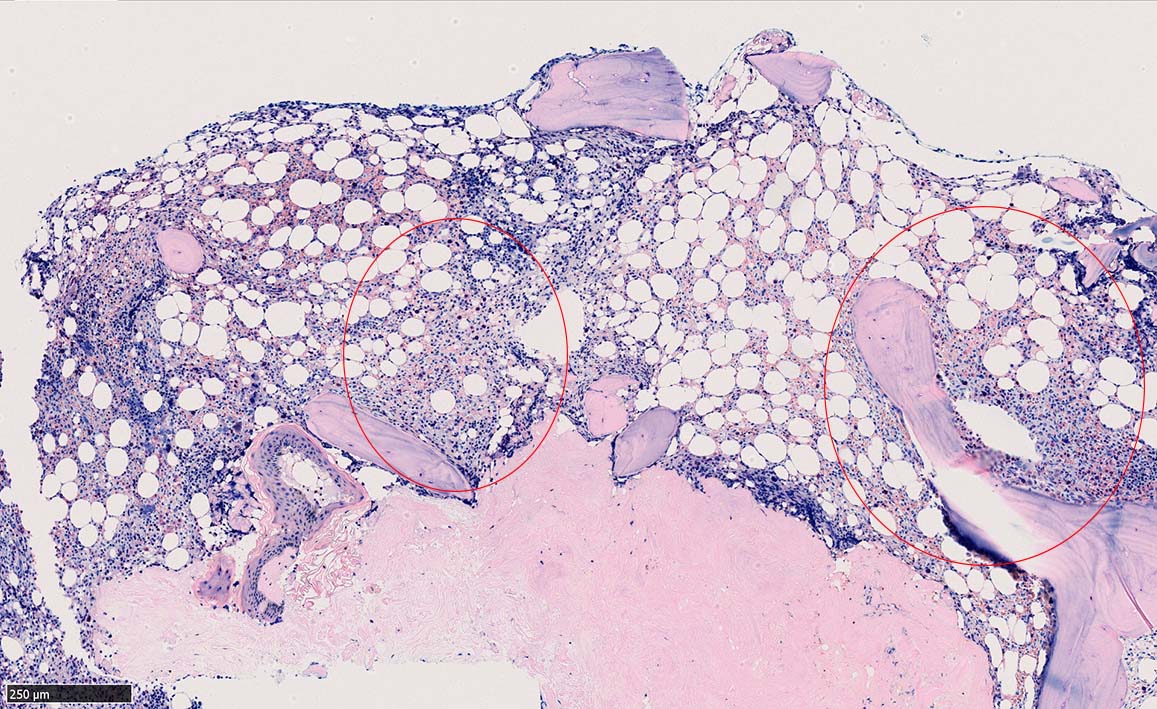

ASD-G 低倍率所見では赤芽球血島は幼若赤芽球の集簇巣が散在する, 顆粒球系細胞(ASDに赤く染色される)は減少,granulopoietic hypoplasiaを呈する.疎な集簇を示すmast cellsの増加がある.

ASD-G陰性の細胞がびまん性に増加しているように見える.

ASD-Giemsa陰性の細胞がシート状に増殖する. 核はクロマチン濃染, 核小体は不明瞭.類円形, 卵円形, くびれを持つ多稜形核, 長円形いびつで屈曲した核, など多彩. 細胞質は淡清色調, 広く淡明. 赤芽球血島は幼若赤芽球のみで形成される異形成像を示す. やや離れて成熟赤芽球が疎な集簇を示す.

Ag染色では, 疎な弾性線維が増生し,増殖細胞を小胞巣状に分画するいわゆる「lymphomatoid pattern」を呈する. 本例では, Mgkに異形成所見がある.

Hairy-FCM のコピー.jpg ASD-up-PAX5ok.jpg びまん性にPAX5陽性の小型B-cellsが増殖している.